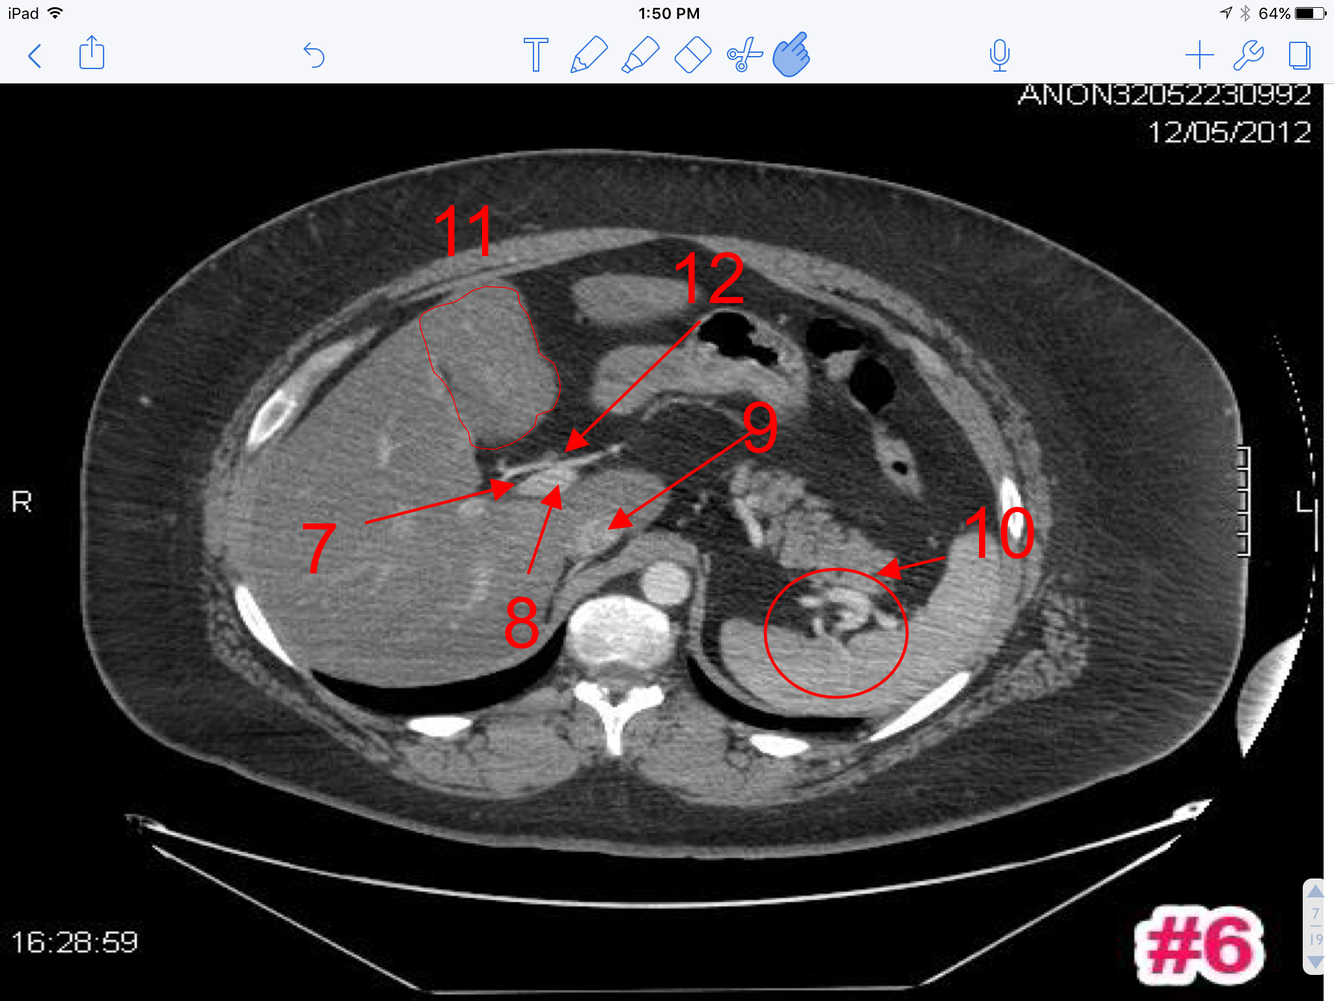

6

A

1. Rt branch of the portal vein

2. Lt branch of the portal vein

3. Intrahepatic inferior vena cava

4. Splenic vessels at the hilum of the spleen

5. Quadrate lobe of the liver (outline)

6. Hepatic artery proper in the porta hepatis